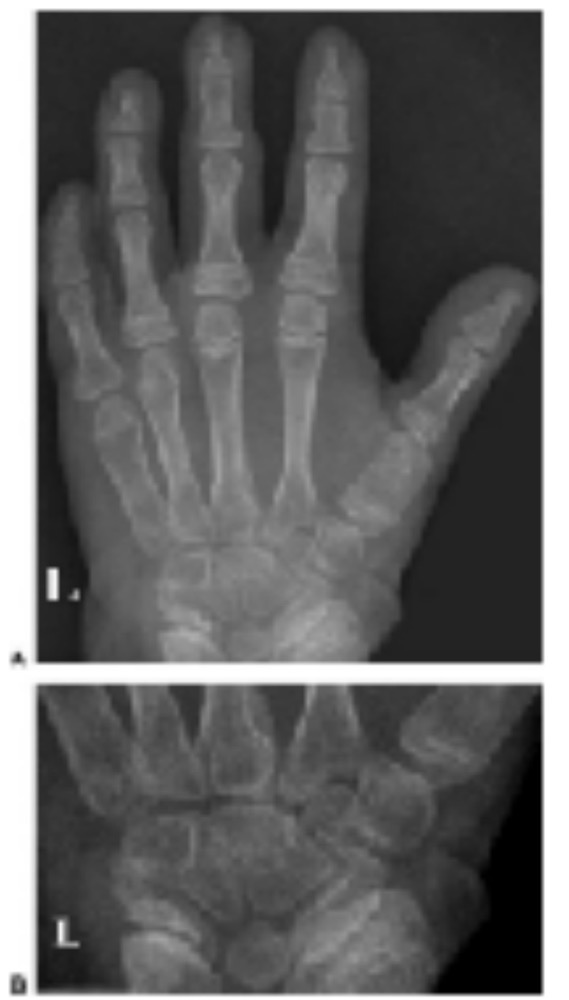

SHOX缺失的临床特征,甚至在同一家庭的受累成员之中,表现出显著的表型可变性。一般而言,女性受累更甚于男性,骨骼的缺陷倾向于随青春期而恶化。SHOX缺乏的X线表型特征包括有,粗糙的小梁骨、胫腓骨近侧端干骺连续、异常的肱骨结节、桡骨和胫骨弓形变化、短掌骨/干骺端开放、腕部骨排列变化、桡骨头的三角形化(表2,图1-3)。在某些研究的LWD和TS病例,未检测出特定的SHOX突变,可能是由于其它基因的参与。在下文中,将进一步详细说明与SHOX单倍体不足相关的各种异常的遗传与X线表现。

图1. (A) 一名10.5岁SHOX突变和软骨骨生成障碍女孩左手X线片,远侧桡骨骺出现倾斜变化。(B)和(C)分别为左右腕前后位X线片。(D)为13岁时右腕侧视X线片,表现出双侧马德隆畸形(右腕更明显一些)。双侧桡尺骨距离增加,桡腕关节呈V形。桡骨远侧干骺端仍然开放,但中间部分融合。两侧腕都在桡腕关节处成角,右腕尺骨也出现了正向变异。

图5. 一名伴有Leri-Weill软骨骨生成障碍的13岁矮身高男孩,手部 (A,B) 和前臂(C,D)X线片表现出典型的马德隆畸形,伴有桡骨弓弯。这些特征包括,两侧的桡骨缩短,远侧干骺端内侧成角和远侧骨骺的异常形状。两侧腕骨存在部分的联合。

图6. 一名患有Leri-Weill软骨骨生成障碍的13岁女孩,双侧马德隆畸形,伴有正向尺骨变异。两侧腕部后前位(A, B)和侧位 (C, D)X线片表明,腕骨角度减小、腕骨楔入远侧桡尺骨之间。桡尺之间的距离加大,两侧远侧尺骨向后侧错位。可见桡骨远侧骨骺呈三角形及生长板形成角度。